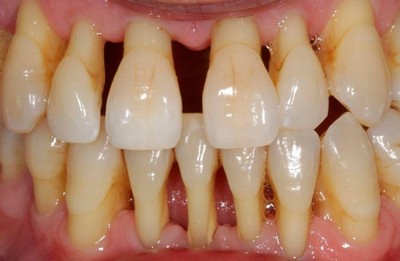

- Если периодонтит является генерализованным, а его стадия — запущенная.

Свищ чаще всего развивается при гранулирующей форме патологии, из-за разрастания грануляций происходит формирование дефекта, разрушаются окружающие ткани.

Если образуется свищ, то это свидетельствует о том, что лечение не действует и микроорганизмы продолжают разрушать зуб.